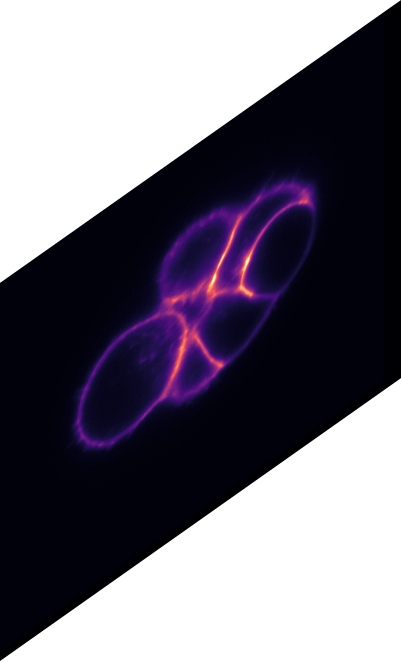

\text{Qualitative Results}